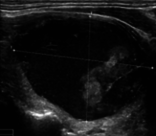

Figure 6 illustrates the segmentation outcomes attained with different neural networks using the same dataset. The enhanced U-Net network proposed in this study is evaluated alongside expert gold standards, Swin-Unet, U-Net, and other well-known network models. The segmentation results from the Swin-Unet network show jagged edges and less smooth nodule edge segmentation, leading to suboptimal outcomes. In the case of U-Net, there are evident under-segmentations with significant discrepancies in the segmented area of some nodules, resulting in inaccurate segmentation results. However, the use of the improved U-Net network introduced in this research produces smoother edges of the segmented thyroid nodules, and the edge contours more closely align with those of the expert gold standard. Moreover, the errors in shape and segmented area are smaller compared to those seen with U-Net and Swin-Unet. The findings suggest that the improved U-Net network provides superior performance in thyroid nodule segmentation.